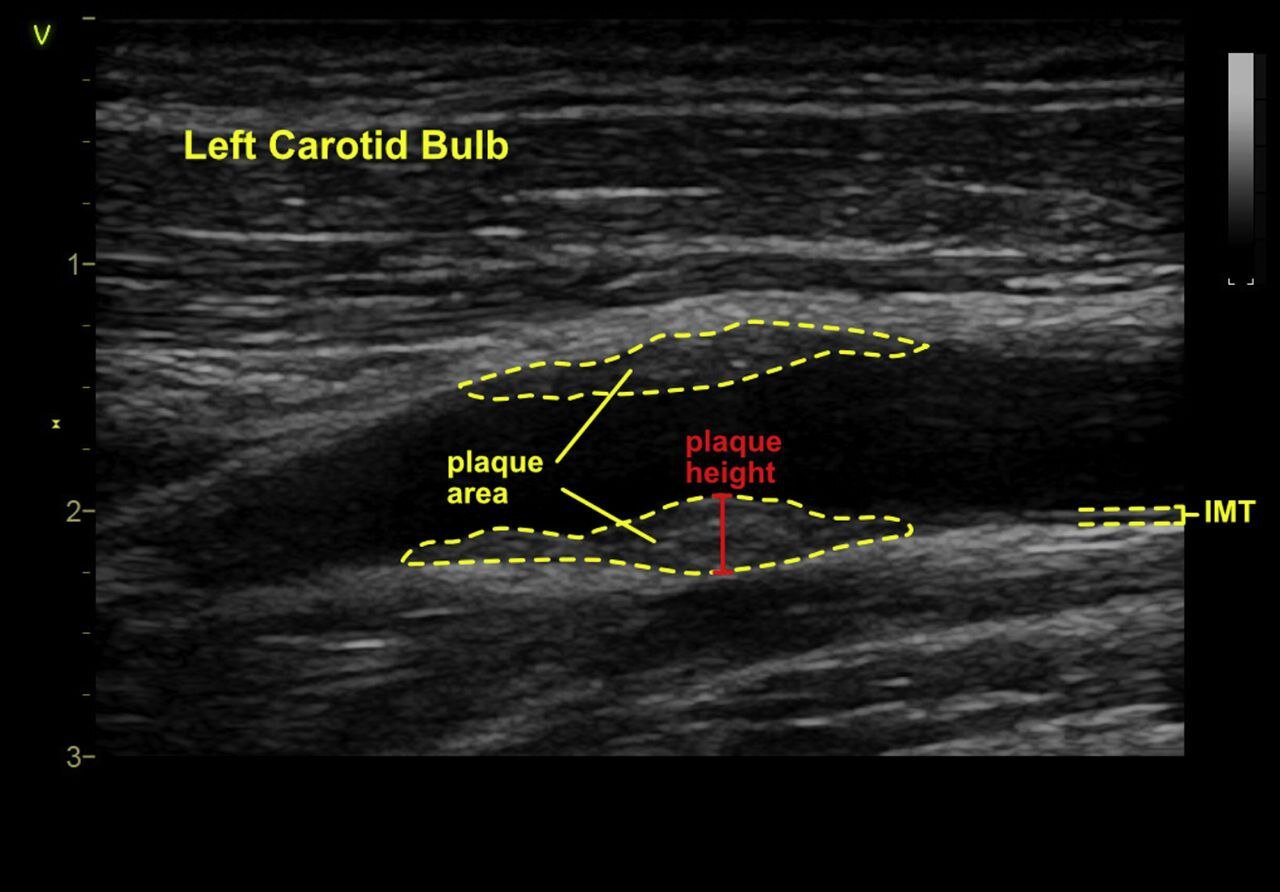

در حالی که پژوهشها نشان داده مشاهدهی مستقیم خود رگها اهمیت بیشتری دارد و برخی متخصصین معتقدند باید با کمک سونوگرافی سهبعدی خود عروق را بررسی کرد.

در حال حاضر امکان بررسی وضعیت عروق با کمک سیتیاسکن و سونوگرافی وجود دارد. اما اغلب خیلی دیر و برای افرادی انجام میشود که همین الان هم دارای درصد قابل توجهی از تصلب شرایین هستند.